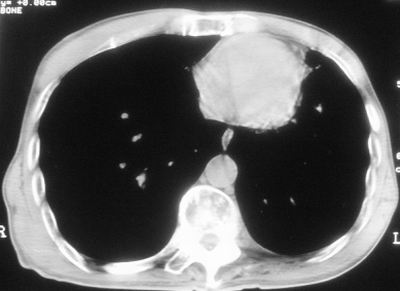

标题: CT11864:男,47岁,反复咳嗽、咯痰、咯血3年,请分析. [打印本页]

标题: CT11864:男,47岁,反复咳嗽、咯痰、咯血3年,请分析.

患者,男,47岁,反复咳嗽、咯痰、咯血3年,再发5天。痰培养未找到真菌、抗酸杆菌、癌细胞。

左肺上叶体积明显缩小,其内见多发透光区,纵隔向左侧移位,左肺下叶多发班片状病灶,边界模糊,1左肺上叶先天肺发育不全,2左肺下叶肺炎,

左肺上叶结核伴肺纤维化,纵隔移位,左肺下叶感染性病变,建议抗炎抗结核后复查,双肺气肿.

以下是引用xulianj在2008-2-25 21:01:00的发言:[br]左肺上叶结核伴肺纤维化有霉菌球形成,纵隔移位,左肺下叶感染性病变,建议抗炎抗结核后复查,双肺气肿.

考虑:左肺慢纤伴霉菌球形成、双肺全小叶型肺气肿。

1)考虑为:左肺上叶肺结核(空洞形成),伴左下肺感染;不排除霉菌感染可能。2)肺气肿。

左肺上叶结核伴肺纤维化空洞形成并左肺下叶感染,纵隔牵拉移位,建议作进一步检查排除左侧肺霉菌感染可能。